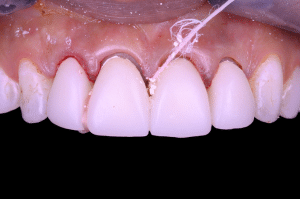

Fig 9

Réponse parodontale à seulement 8 jours post opératoire. L’élimination de tout le ciment en excès à permis une rapide cicatrisation parodontale.